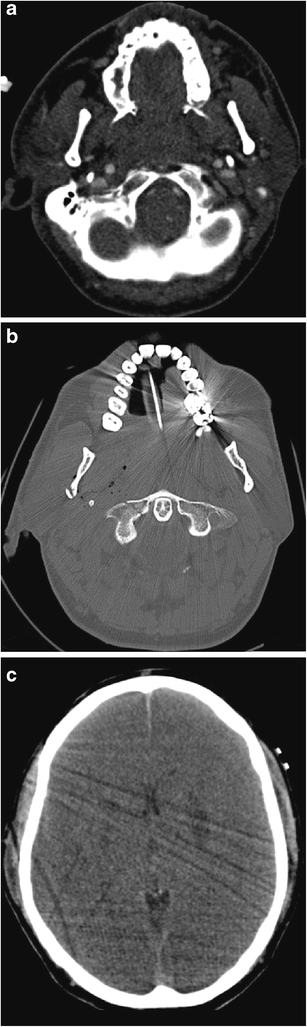

a Axial MDCTA image of a 9-year-old patient who sustained accidental penetrating injury by a wooden stick to zone 2 of the right neck. The stick was removed at the time of the injury by the patient’s friend but there is dissection occlusion of the right internal carotid artery; only the external carotid artery, one of its branches and the vertebral artery are visible on this side. The normal left internal carotid artery is annotated for comparison (blue arrow). The patient escaped any significant complicating cerebrovascular ischaemic event. b Axial source image of two-dimensional time of flight MR angiogram of the same patient as in a, performed 4 years later as part of follow-up assessment. The previously injured right internal carotid artery has re-canalised (in keeping with the natural history of dissection injury) but exhibits residual focal stenosis (red arrow) compared with the normal contralateral left internal carotid artery (blue arrow)